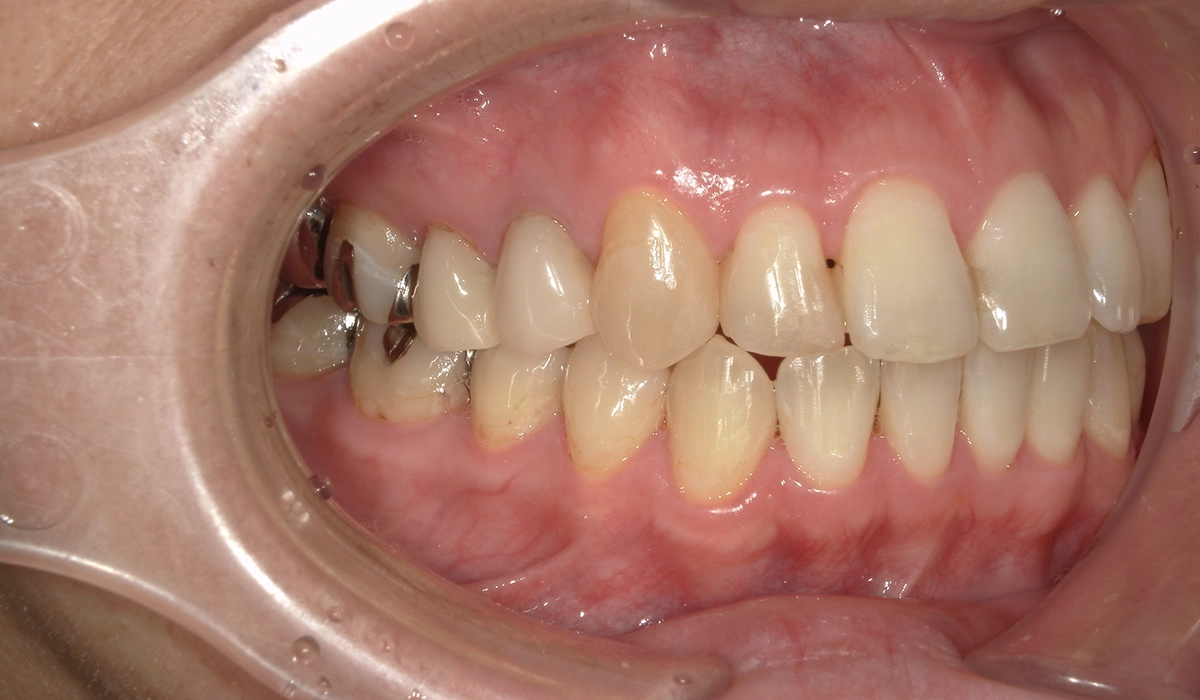

術前:右側

術後:右側